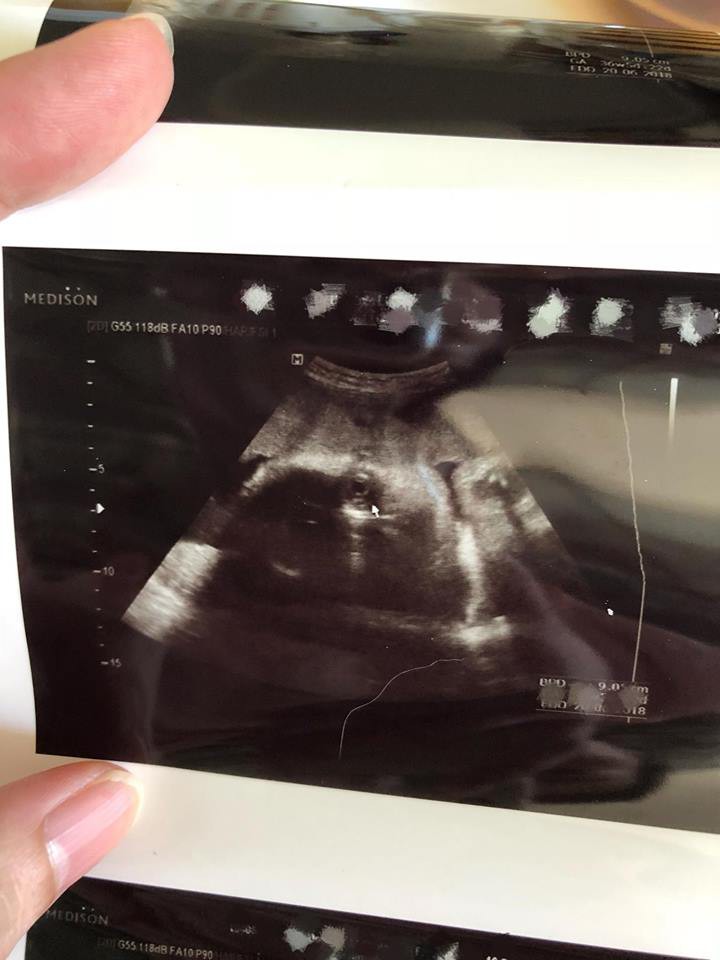

此外,翠翠還Post 出一張胎兒超聲波照,並留言表示:「去了檢查,一切非常順利!需然未到預產期,但胎兒已經有6磅,醫生還說如果萬一有咩事今晚就要生,已經好安全不用擔心,我個心都定啲,希望到時 bb 出世有8至9磅。相中見到 bb 面珠登好肥。。。眼大大同我好似(心理作用)一直都同大家分享長胎不長肉餐單,是標準磅數但重磅 bb ,而不是媽媽超磅 (重超過30磅),bb 重磅。當然都好過媽媽超磅,bb 輕磅。各位要努力!」